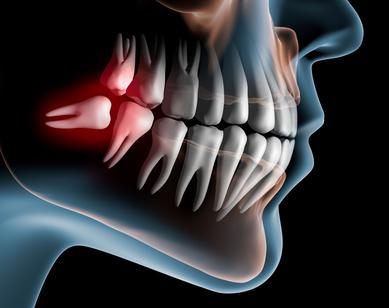

El mayor problema es la falta de espacio, la muela del juicio busca una manera de salir y acomodarse , pero muchas veces no puede. Esto conlleva que la muela salga mal posicinada o no salga completamente o lo que es peor que salga dañando las muelas vecinas. Debido a esto se acumula más suciedad en esa zona por lo que causan más problemas.

Cuando las Muelas del juicio erupcionan o salen parcialmente , provocan la entrada de comida y bacterias entre el diente y la encía , causando Caries e infección , lo que resulta en dolor , trismus ( Imposibilidad de abrir la boca completamente ), dolor de oído y garganta y en muchos casos malestar general.

Al salir los terceros molares pueden dañar los dientes adyacentes y movilizarlos.

Lo más común en estos casos en es tomarse un antiflamatorio , en la mayoria cobertura antibiotica por si acaso. Sin embargo cuando el dolor o los sintomas persisten o duran , hasta el punto de ser terribolemente molesto , entonces deberiamos acudir a nuestro dentista para realizar la extracciones de la muela del juicio. En las muelas del juicio inferiores debemos tener especial cuidado y si es posible acudir a un especialista ya que la proximidad entre el diente y el nervio dentario , se puede convertir en un riesgo. Por lo que muchos Dentistas os pediran que os hagais un TAC para comprobar la posicion en tres dimensiones del nervio dentario y concretar si existen algun peligro.